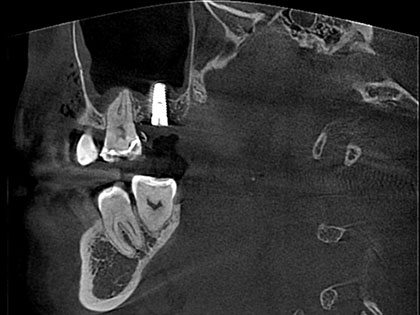

親知らず抜歯症例

親知らず抜歯症例6

左右下親知らずを抜歯したいとの事で来院、治療を希望された患者様の症例になります